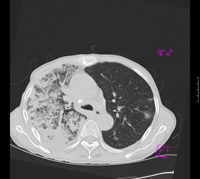

标题: CT9563:女67岁,咳嗽咯白痰伴纳差一月。右肺呼吸音低可闻及 [打印本页]

女67岁,咳嗽咯白痰伴纳差一月。右肺呼吸音低可闻及湿罗音。白细胞及淋巴细胞不高,无发烧

1、右上胸廓塌陷,纵隔气管右移

2、病灶靠后方,一般结核多见一点

3、病灶内,纵隔内有少许钙化灶

3楼的肺细支气管肺泡癌也不能完全排除,毕竟患者年纪大,病史短,临床上感染症状不明显,建议短期内复查吧